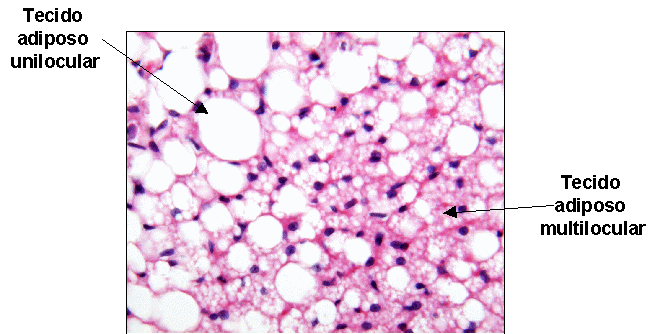

Tejido Adiposo.Jocelyn Aldana Se clasifica en dos tipos, sea que está constituido por adipocitos uniloculares o multiloculares."Tejido adiposo blanco o unilocular"* Cada célula de grasa unilocular contiene una gota de lípido que confiere el tejido adiposo compuesto de estas células un color blanco.* Tiene en abundancia vasos sanguíneos, que forman redes de capilares en todo el tejido* Las membranas plasmáticas de las células adiposas uniloculares contienen receptores para varias sustancias, entre ellas insulina, hormona de crecimiento, noradrenalina y glucocorticoides, que facilitan la captación y liberación de ácidos grasos libres y glicerol.* La grasa unilocular se halla en las capas subcutáneas de todo el cuerpo. También se encuentra en acumulaciones en sitios característicos que dependen del sexo y la edad."Tejido adiposo pardo o multilocular"Está compuesto de células de grasa multiloculares que almacenan grasa en múltiples gotitas.El tejido adiposo pardo es muy vascular por que los vasos se localizan cerca de los adipocitos. En recién nacidos, la grasa parda se localiza en las regionesdel cuello y el área interescapular, debido a que es éste tejido el que los mantiene calientes. El tejido adiposo pardo se vincula con la producción de calor corporal por el gran número de mitocondrias en los adipocitos multiloculares que constituyen este tejido.La termogenina, en las mitocondrias, permite el flujo retrógrado de protones en lugar de utilizarlos para la síntesis de ATP, como resultado del desacoplamiento de la oxidación por la fosforilación, el flujo de protones genera energía que se dispersa como calor.